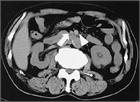

1. SMA閉塞症の疫学と初期診断:発症頻度は毎年5.6~8.6人/10万人と低いが、死亡率は24~94%と予後不良で、生命予後の改善には早期診断・治療が求められる(推奨度1J)

1. SMA閉塞症の画像診断による確定診断:問診・理学的所見・血液検査は必須であるが確定診断に至ることは困難であり、確定診断には画像評価が必須である(推奨度1J)